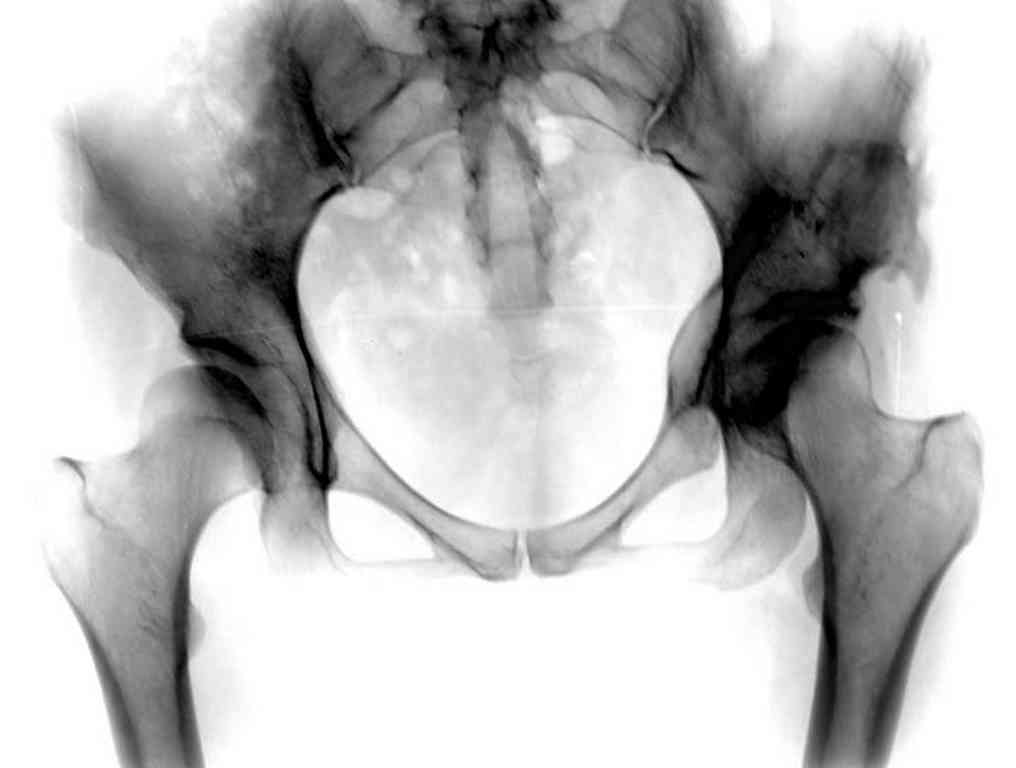

Типичная концовка проигнорированного диспластического состояния сустава. Дисплазия тазобедренного сустава часто встречающаяся патология у жителей Центральной Азии вследствие тугого пеленания в детстве. Традиционно ребенок находится в течение дня в так называемой кроватке "бешик", удобной в быту, но она впоследствии приводит к недоразвитию тазобедренного сустава.

Это первые признаки начала деструкции сустава, и возможно, аналгетики помогут для купирования болей, но в течение очень короткого времени от сустава ничего не останется, и в дальнейшем останется только артропластика.

При более сохранном суставе от дальнейшего разрушения можно было бы сохранить только периориентацией нагрузки на сустав - Периацетабулярной Остеотомией .

Данный сустав в начальной стадии разрушения, но все-таки я бы сделал обзорный таз и отдельные снимки сустава в 30 градусной абдукции и аддукции. Также снимки с внутренней и наружной ротацией для оценки состояния головки бедра.